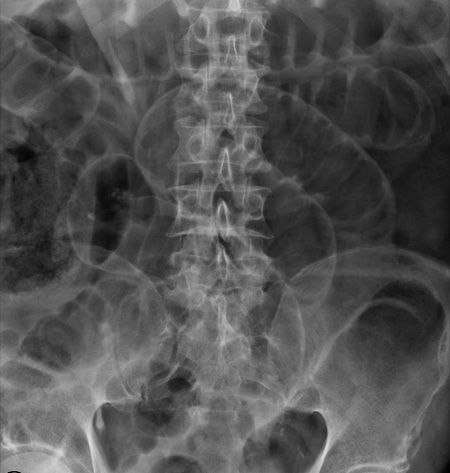

X-RAY QUIZ: Which finding is present on this image?

Start Quiz bit.ly/36i1txn